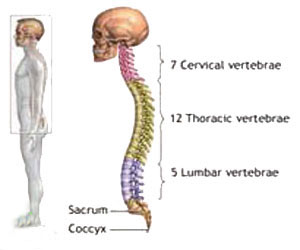

هنگامی که در مورد سلامتی صــحبت بـه میـان مـی آیـد بی تـردید وضــعیت صحیـح قرارگـیـری بـدن شـمـا هـنـگام فعالیت های گوناگون در رأس فهرست عوامل مهم سلامتی قـرار خـواهد گـرفـت، زیـرا بـه انـدازه تغذیه مناسب، ورزش، پـرهـیـز از مواد الکلی و سیگار در حفظ سلامتـی بـدن موثر می باشد. وضـعـیت صحیح قرارگیری اندام ها کمک مـی کند تا کـارهـایـتـان را بـا انـرژی بیـشتـر و اسـتـرس و خـستگی کمتر به انجام رسانید...